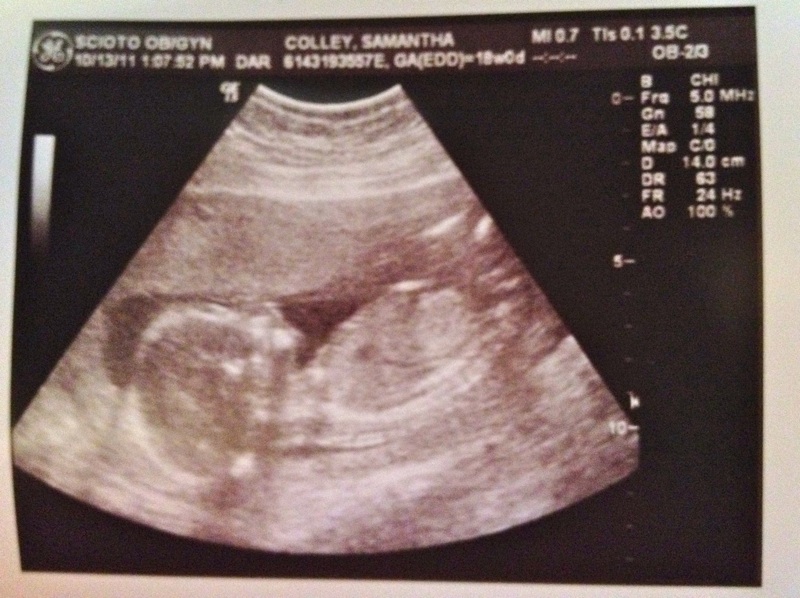

Last Thursday, Baby Colley decided to finally show us the goods and solved “The Great Gender Mystery.”

Drumroll please . . . . . . . it’s a boy!!!

I should also let you know that in addition to gender, the doctor’s appointment went well and he is measuring spot on with his due date and looks healthy from all aspects. My cervix is also staying put and looking “terrific” according to my doctor. So everyone is happy and healthy so far. Yay!